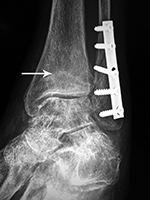

Left ankle syndesmotic screw fracturing |

22 year-old man with syndesmotic screw placement for medial avulsive ankle injury. The screws fractured and loosened and were later removed. |